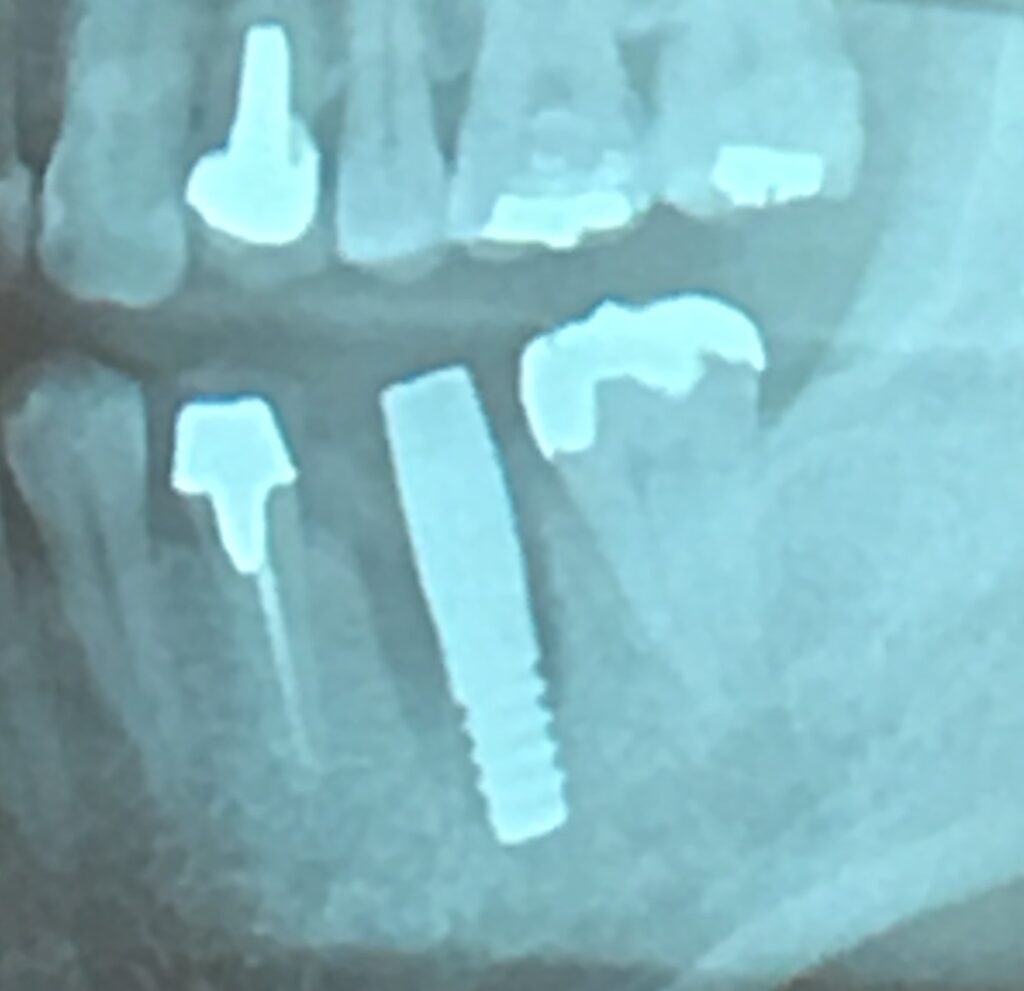

●下顎神経障害

下顎の奥歯の下に下顎管という神経や動脈が通っている骨のトンネルがあります。

インプラントを埋め込むために穴を開けますが、このとき下顎管を傷つけてしまうと、そこを通っている神経が傷つくことがあります。

すると、下唇や顎先の感覚が鈍くなってしまうリスクがあります。

●骨造成手術

下顎の場合も、骨の厚みが足りない場合は、骨の厚みを回復させなければなりません。

下顎に対しては、ご自身の他の部分の骨や人工骨材料を埋め込み、メンブレンという膜やチタン性のメッシュで囲うGBRという骨造成手術などが選ばれます。

移植骨が安定化しなければ、骨の厚みを得ることはできず、インプラント治療が困難になるデメリットがあります。